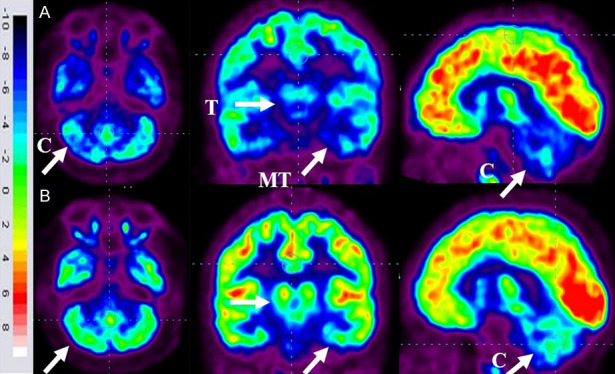

FDG-PET CT掃描腦部對比分析

86名患者的家長同意在干預6個月后重復進行FDG-PET CT掃描以進行比較分析。干預前,這些患者的FDG-PET/CT掃描顯示雙側(cè)內(nèi)側(cè)顳葉皮層、丘腦和小腦的代謝活動降低[代謝減退]。此外,它們還表現(xiàn)出尾狀頭、殼核、眶額皮質(zhì)和前額葉皮質(zhì)的代謝活動增加(代謝亢進)。

干細胞移植六個月后,所有患者的大腦活動均得到改善。此前,代謝低下區(qū)域[內(nèi)側(cè)顳葉皮質(zhì)、丘腦和小腦]顯示FDG攝取增加,而代謝亢進區(qū)域[尾狀頭、殼核、眶額皮質(zhì)和前額葉皮質(zhì)]顯示FDG攝取減少(圖6)。在進行T檢驗時,發(fā)現(xiàn)干預前后這些區(qū)域的平均SUV出現(xiàn)了統(tǒng)計學上的顯著變化[P<0.05]。

A.頂行:標有箭頭的藍色區(qū)域表明代謝低下。B. 下排:用箭頭標記的綠色區(qū)域表明細胞移植后新陳代謝得到改善。

FDG PET CT大腦掃描被用作接受多劑量細胞移植的患者的額外結(jié)果測量。它用于監(jiān)測細胞水平干預的效果。這種功能性神經(jīng)影像技術(shù)利用18-FDG來研究大腦的代謝活動。我們對86名患者進行了FDG PET CT掃描腦部的比較研究,結(jié)果證明了其對新陳代謝的平衡作用。代謝低下的區(qū)域顯示代謝增加,而代謝亢進的區(qū)域顯示代謝減少。